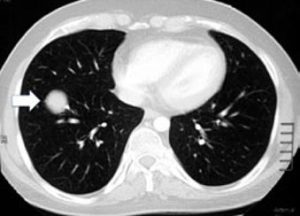

Ortopedik onkolojide BT’nin bir diğer önemli kullanım alanı da habis kemik ve yumuşak doku tümörlerinin akciğerlere sıçrayıp sıçramadığının (metastaz) araştırılmasıdır. Normal akciğer röntgeninde, 1 cm çapından küçük nodüller görülemediğinden, metastaz taraması için mutlaka ince kesitli bilgisayarlı akciğer tomografisi kullanılmalıdır.